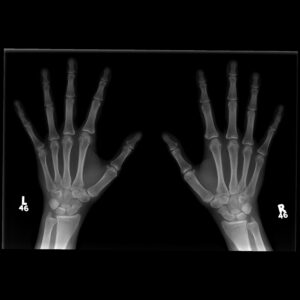

Normal hand Xray

Description & Notes

Categories

Tags